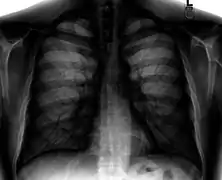

A chest radiograph showing bronchopulmonary dysplasia.